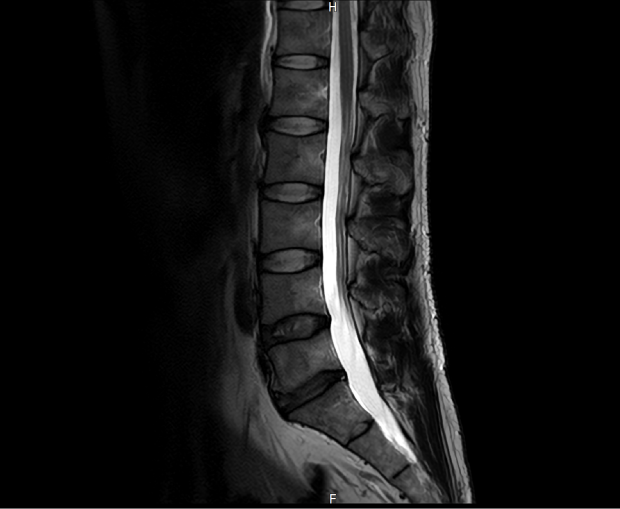

혹시나 싶어 허리MRI도 찍어봤으나 허리는 크게 문제되보이진 않았습니다.

요추 MRI 상태입니다.

근전도에선 요추5번인가에 왼쪽 이상소견이 나왔다고 하는데 증상이 원래 이런식으로 나타날수가 있는건지 모르겠고 그리고 혈류검사에서는 양쪽 다리에 둘다 복재정맥에 정맥부전이 보이던 상태로 수술을 권하더라구요. 대체 어디서부터 손대야할지도 모르겠고 미치겠습니다...